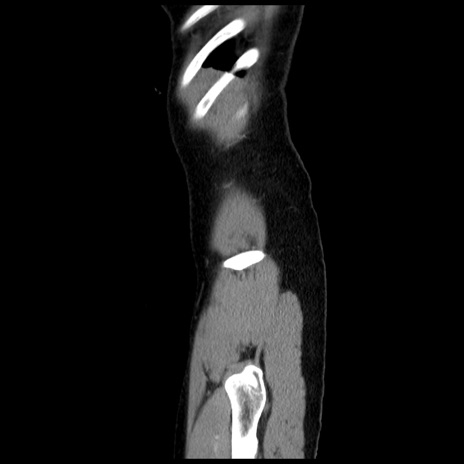

症例10(矢状断像)

症例

【症例】 50歳代女性

【主訴】 腹痛

【現病歴】前日生レバーを食べた。今朝に排便あり。 昼前に突然発症の腹痛を生じ、当院救急外来を受診した。

【既往歴】 子宮筋腫にてで子宮全摘後

【身体所見】 意識清明、腹部:平坦、軟、下腹部やや左を中心に圧痛・反跳痛あり、筋性防御あり

【データ】WBC 7800、CRP 0.07